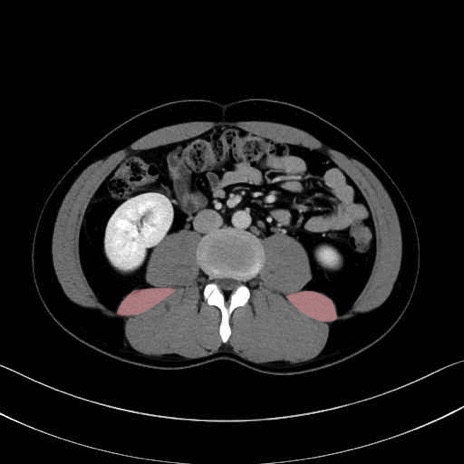

腰方形筋 (Quadratus lumborum)

大腰筋 (Psoas major)

腸骨筋 (Iliacus)